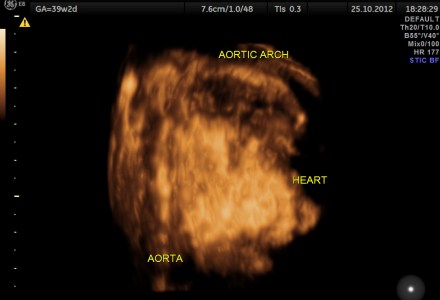

Hypoplastic Left Heart Syndrome (H.L.H.S.)